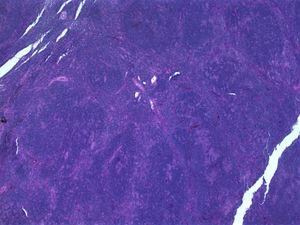

لمفومة جريبية حلت محل عقدة لمفاوية.